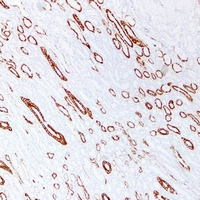

(Immunohistochemical analysis of Cytokeratin 19 staining in human kidney formalin fixed paraffin embedded tissue section. The section was pre-treated using heat mediated antigen retrieval with sodium citrate buffer (pH 6.0). The section was then incubated with the antibody at room temperature and detected using an HRP conjugated compact polymer system. DAB was used as the chromogen. The section was then counterstained with haematoxylin and mounted with DPX.)